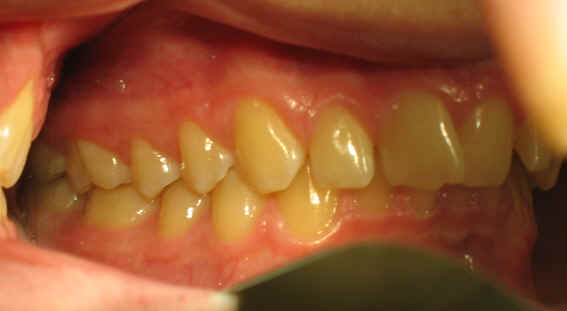

Pre-op 2009/04/18